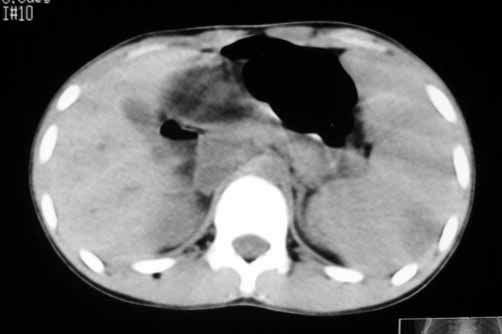

以下是引用余辉在2007-5-22 20:42:00的发言:[br]黄疸,脾脏巨大,病程短,考虑急性肝脏疾病或急性溶血性疾病,建议查肝功能及相应病毒抗体抗原

以下是引用zhangzhongshou在2007-5-22 21:04:00的发言:[br]1、脾肿大[br]2、脾脏低密度影,血管瘤?脾梗塞不能除外,建议增强扫描。

以下是引用dyqct在2007-5-22 20:45:00的发言:[br]巨脾,可疑梗塞,建议增强、查血象进一步检查

以下是引用liuyue在2007-5-23 7:57:00的发言:[br]腹主动脉周多个肿大淋巴结,脾大伴三角形低密度影,肠腔积气,考虑:1淋巴瘤2脾大伴梗塞3肠腔积气(肿大淋巴结压迫所致)